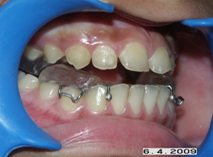

Correction of jaw positions during growth

In growing patients if the lower jaw is small in size or backwardly placed then the position of the lower jaw can be improved using certain removable appliances called Functional appliances. Not all patients are suited for this kind of treatment, case selection is important.

Again in growing patients sometimes the growth of jaws if improper can be restricted or encouraged using certain orthopedic appliances, which are metal frameworks from which elastics are engaged.

Appliances to correct jaw realtions